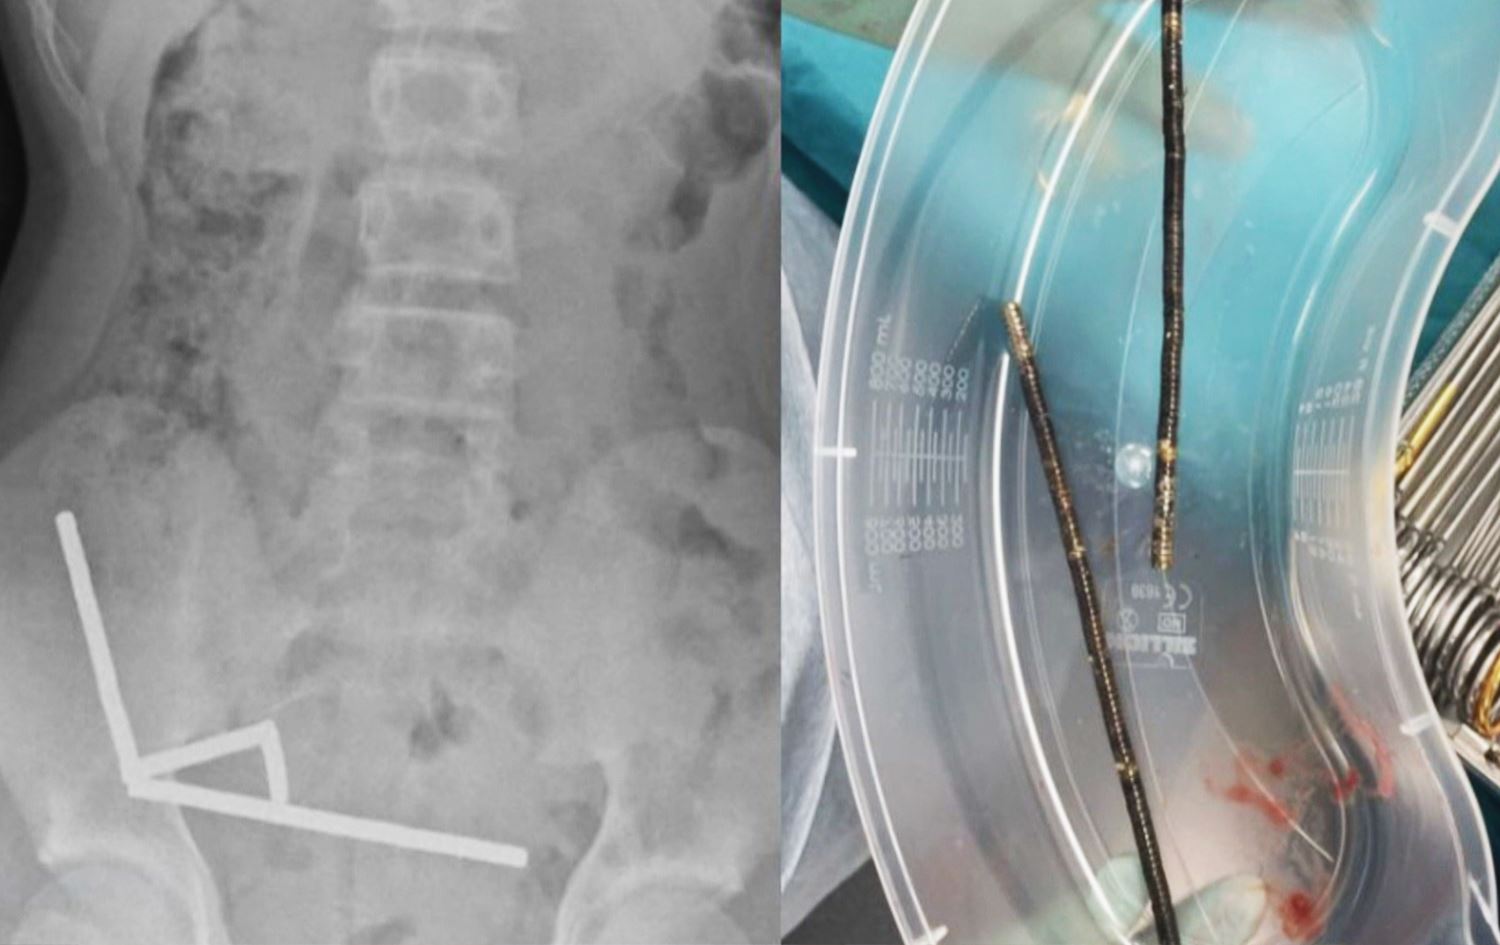

نەخۆشخانەیەک لە نیوزلاند رایگەیاند، نەشتەرگەرییەکیان بۆ نەوجەوانێکی تەمەن 13 ساڵ کردووە و نزیکەی 100 موگناتیسان لە ریخۆڵەکانیدا دەرهێناوە، کە بەهۆیەوە بەشێک لە شانەکانی ریخۆڵەی لەناوچووبوو.

نەخۆشخانەی تاورانگا لە نیوزیلاندا ئاماژەی بەوەدا دوای ماوەیەک لە قوتدانی موگناتیسەکان، کچەکە تووشی ئازارێکی توندی سک و رشانەوە بووە، دوای گەیاندنی بە نەخۆشخانە و ئەنجامدانی پشکنینی پزیشکی، دەرکەوت کە موگناتیسەکان لەنێو ریخۆڵەکانیدا بەیەکەوە نووساون و بوونەتە هۆی دروستبوونی چەندین کون لە کۆئەندامی هەرسیدا.

نەخۆشخانەکە ئاشکرای دەکات، نەشتەرگەرییەکی بەپەلەیان بۆ ئەنجامدا و سەرکەوتووانە سەرجەم 100 موگناتیسەکەیان لە سکی دەرهێنا، ئێستا باری تەندروستیی کچەکە جێگیرە و لەژێر چاودێریی پزیشکیدایە.